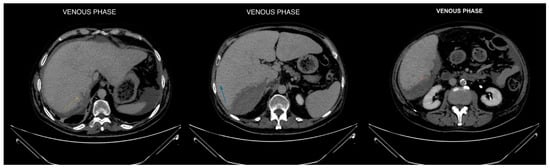

Figure 1. Axial phases without and with contrast CT images demonstrating hepatomegaly with a liver length of approximately 25 cm. The liver parenchyma displays a finely and diffusely heterogeneous density.

Diagnostics 14 02088 g001